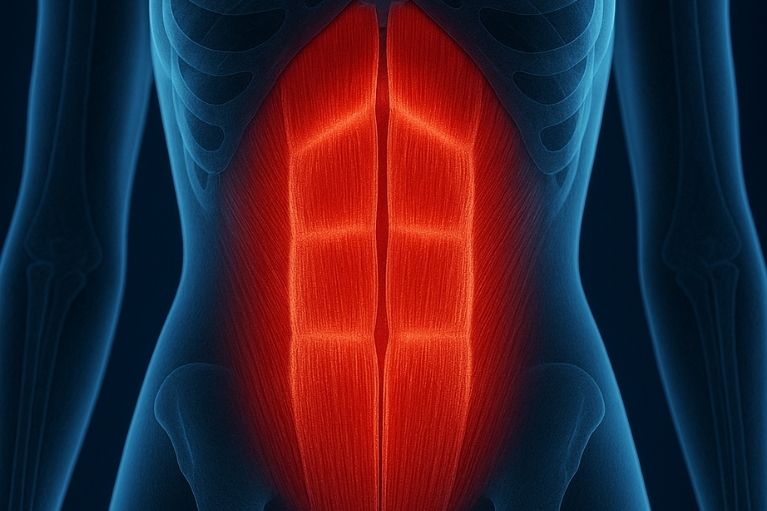

É a separação dos músculos retos do abdômen. Muito comum após a gravidez, mas ocorre também em outras situações. A correção por via robótica traz um resultado estético muito bom.